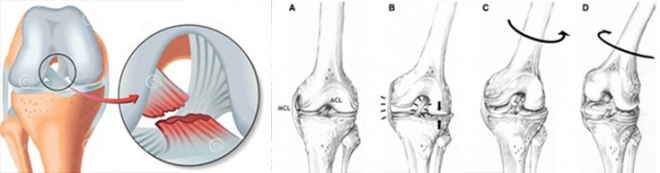

Ο πρόσθιος χιαστός σύνδεσμος εκτός του ότι συγκρατεί το γόνατο για να μην μετατοπίζεται, να «φεύγει» προς τα εμπρός, αποτελεί και το σύνδεσμο πέριξ του οποίου περιστρέφεται το γόνατο κατά την κίνηση κάμψεως-εκτάσεως. Γιατί όπως έχει ήδη αναφερθεί, το γόνατο κατά την κάμψη-έκταση, ολισθαίνει ελαφρώς και περιστρέφεται (με άξονα τον πρόσθιο χιαστό).

Σε κακώσεις κυρίως αθλητικές, επισυμβαίνει στροφική κάκωση του γόνατος και υφίσταται ο πρόσθιος χιαστός ρήξη συνήθως στην έκφυσή του ή στη μεσότητα.

Συχνά συνυπάρχει και βλάβη του έσω πλαγίου συνδέσμου και ρήξη του έσω ή έξω μηνίσκου (ατυχής τριας).

Το γόνατο μετά την κάκωση εμφανίζει ταχύτατα διόγκωση λόγω αίμαρθρου. Δηλαδή ενώ στη ρήξη του μηνίσκου η συλλογή υγρού είναι βραδεία, στη ρήξη χιαστού το γόνατο πρήζεται πολύ γρηγορότερα. Η κάμψη-έκταση επηρεάζονται σημαντικά αν και ο πόνος στη βάδιση είναι ήπιος (συνήθως χρειάζεται λόγω πόνου μια βακτηρία (πατερίτσα). Αφού ελέγξουμε τον περιορισμό της κάμψης-έκτασης, με το γόνατο σε κάμψη που να προσεγγίζει τις 90⁰, ακινητοποιούμε το πόδι (καθήμενοι επάνω στο πόδι) και με τα δύο χέρια έλκουμε την κνήμη προς το μέρος μας.

Στο φυσιολογικό γόνατο η κνήμη δεν μετακινείται. Στο πάσχον «έρχεται» εμπρός. Συχνά η επαναφορά του ποδιού (γόνατος) στην πρότερη θέση, συνοδεύεται από «γδούπο» (θόρυβο ανάταξης).